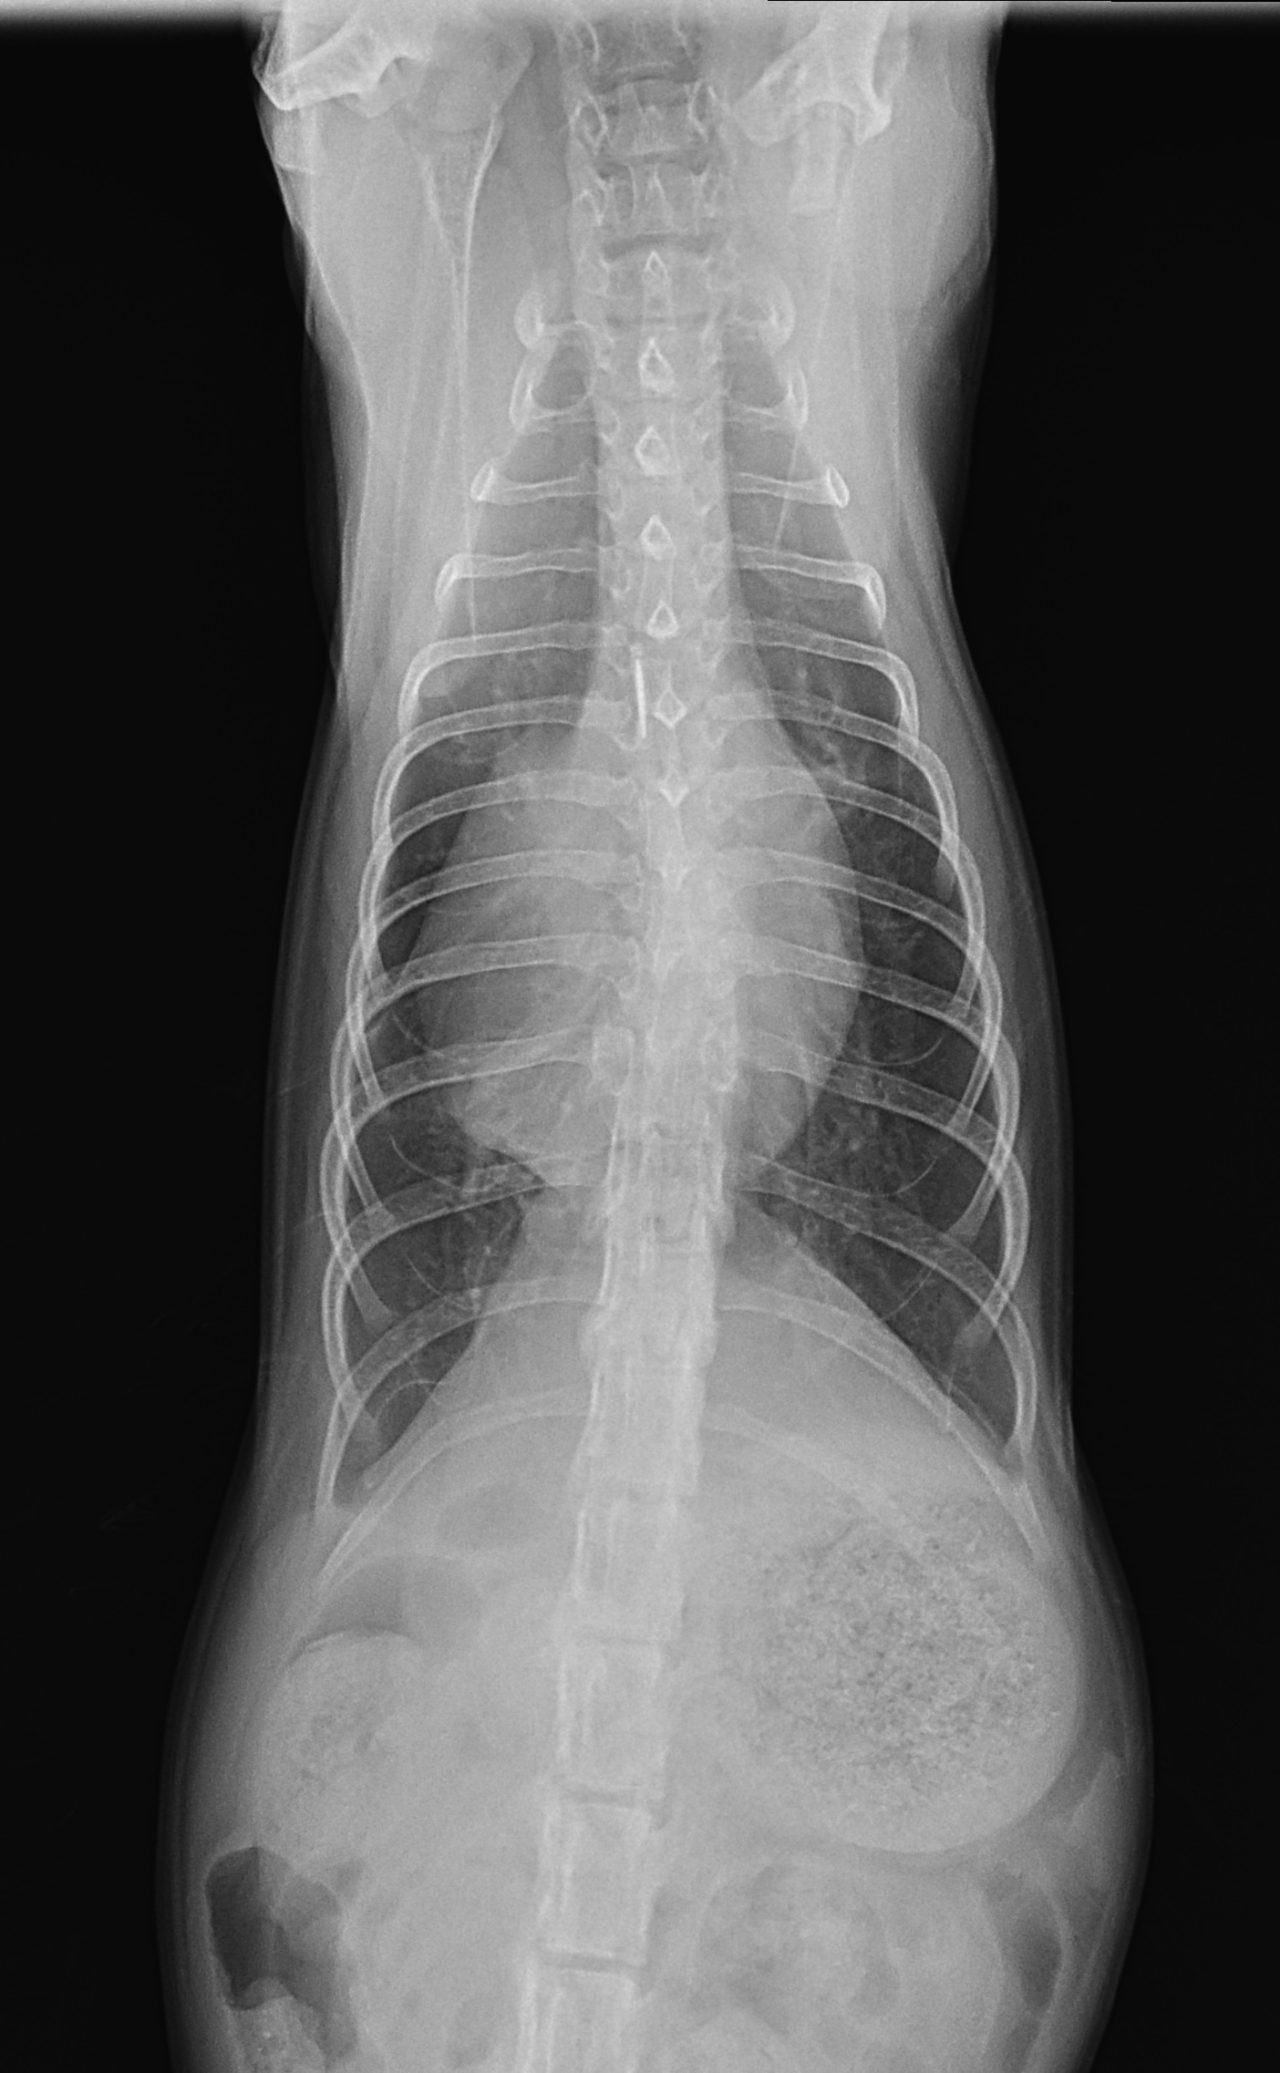

先天性心嚢横隔膜ヘルニア

若い猫が、普段はとても元気だけど、遊んだ後などに咳をする。呼吸が早くなる時がある。などの呼吸器症状で主治医を受診しました。エックス線検査の結果、心嚢横隔膜ヘルニアと診断されました。主治医より、外科的な対応のため紹介受診となりました。腹部正中切開の後、心嚢内に逸脱した、肝臓、胆嚢、小腸を腹腔内に戻し、横隔膜を再建しました。術後には、再拡張性肺水腫という病態が発生する可能性があるため、24時間体制で、患者さんを見守ります。幸い、肺水腫の傾向はみられず、5日目に無事に退院となりました。周術期には一時的に低酸素症に陥ったり、二酸化炭素濃度が上昇したりと、不安定な場面もありましたが、小さな体で本当によく頑張ってくれました。これで、普通の子猫としてどんどん大きく成長してくれると思います。本当によかった。